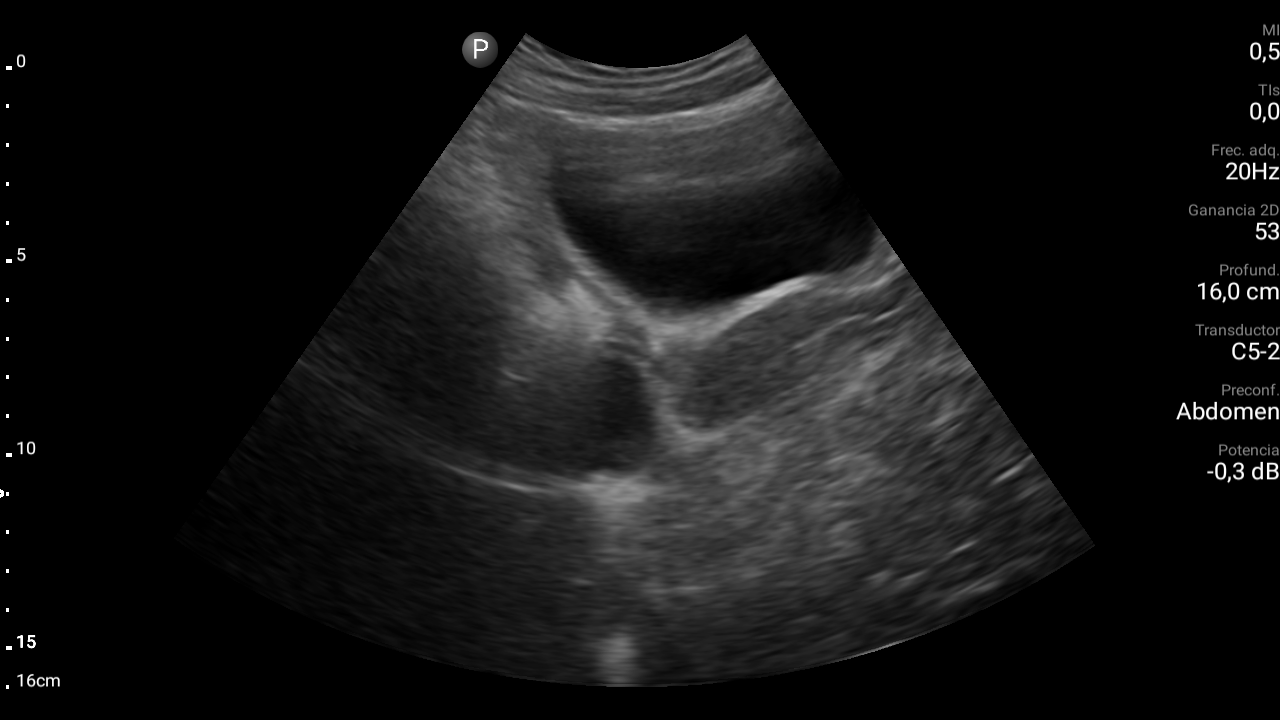

En ecografía abdominal se observa masa hipoecoica dependiente de útero por lo que se remite de forma preferente a ginecología.

En ginecología le realizan ecografía transvaginal, siendo diagnosticada de mioma uterino.